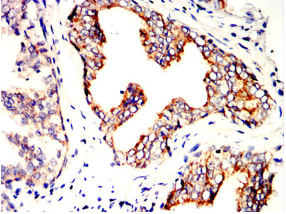

| AC3520 | SLC7A3 Mouse Monoclonal antibody[6H3B7] | 100ug | $367 | 10days |

| AC3520 | SLC7A3 Mouse Monoclonal antibody[6H3B7] | 200ug | $660.6 | 10days |